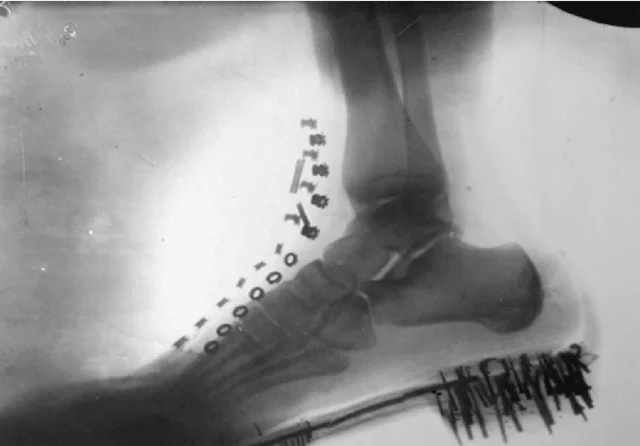

• Raigos X

Raigos X

Els raigs X són capaços de travessar els materials sòlids, com els metalls i els ossos, i es van utilitzar inicialment per al diagnòstic mèdic. Els raigs X van tenir un gran impacte en el món, ja que van obrir les portes a noves possibilitats en medicina. Va permetre a la comunitat científica veure a través dels teixits i els ossos per comprendre com funciona el cos humà, així com per diagnosticar i tractar malalties.